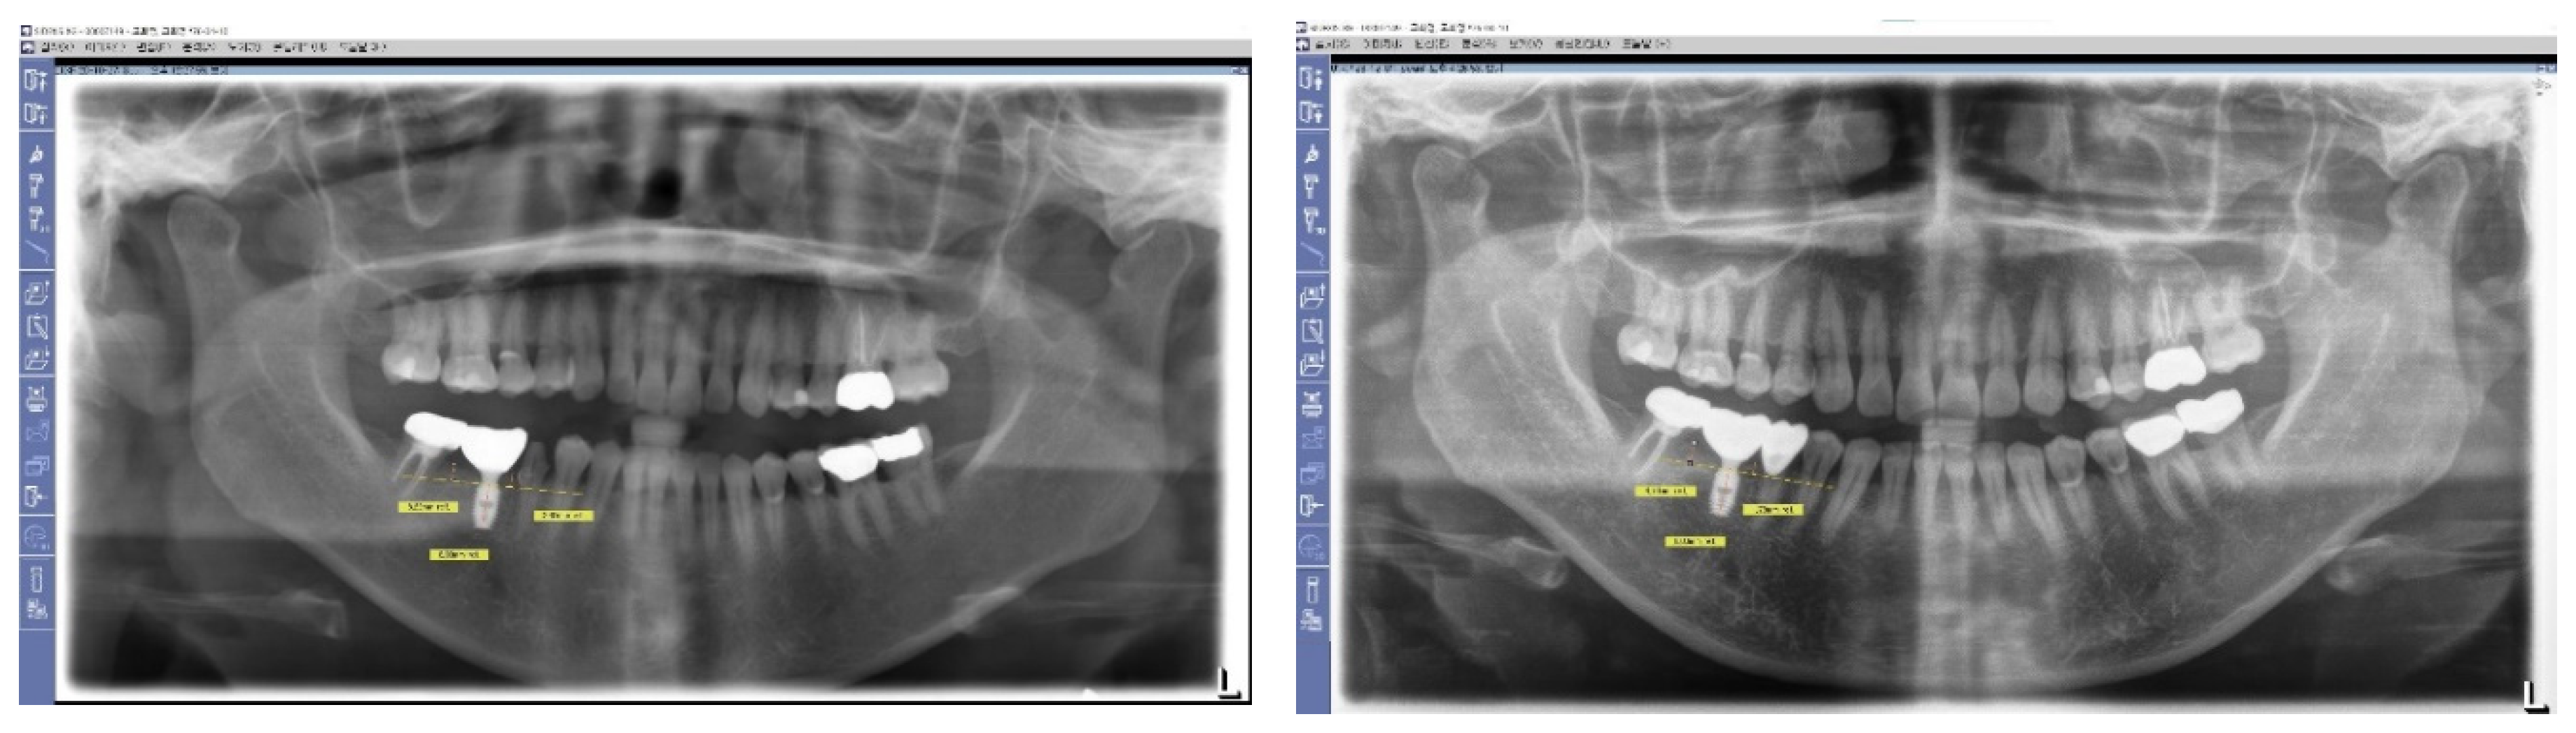

Figure 9. X-Ray Sequence of Healing Abutment Changes. This series of X-rays illustrates the procedural sequences for implant placement and subsequent adjustments. Initially, healing abutments measuring 5 mm in diameter and 2.5 mm in height were placed and covered with primary flap closure. After three months, a second operation was undertaken for the prosthetic procedure. During this stage, the sites were uncovered and longer healing abutments, maintaining the same profile as the initially embedded abutments, were connected to prepare for final prosthesis installation.